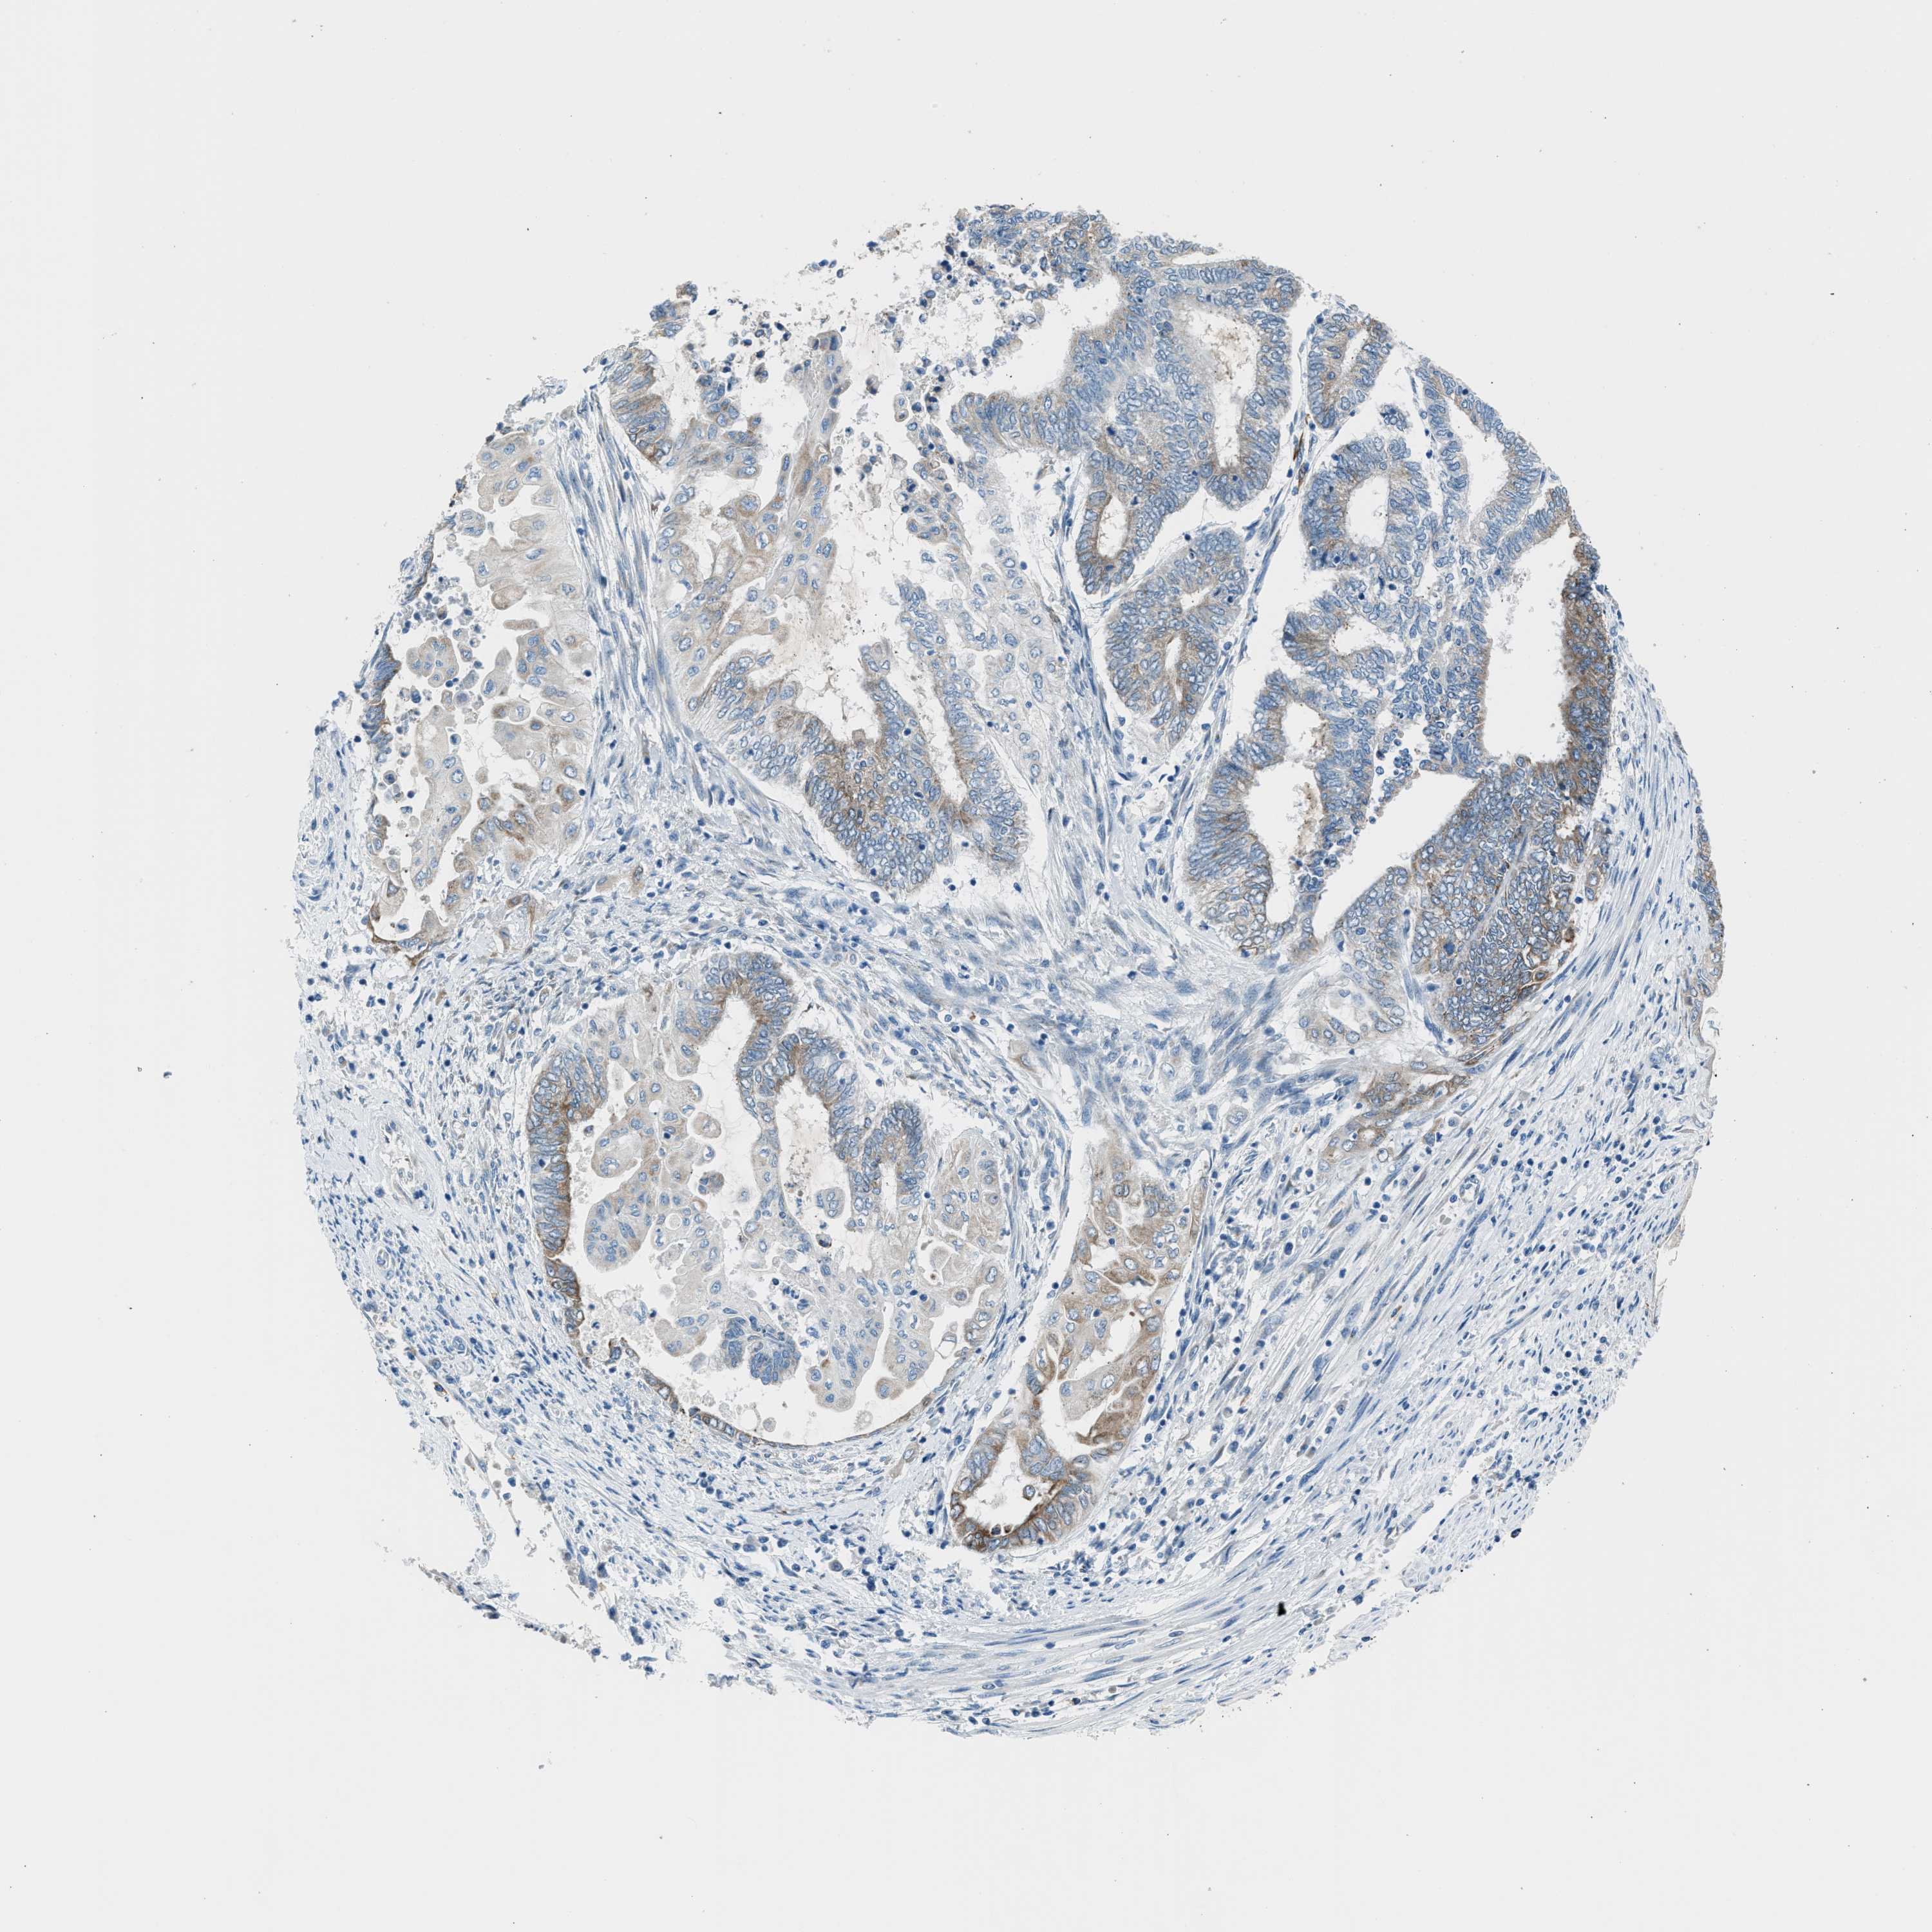

ENDOMETRIAL CANCER - Protein expressioni

A mouse-over function shows sample information and annotation data. Click on an image to view it in a full screen mode. Samples can be filtered based on level of antibody staining by selecting one or several of the following categories: high, medium, low and not detected. The assay and annotation is described here.

Note that samples used for immunohistochemistry by the Human Protein Atlas do not correspond to samples in the TCGA dataset.

Antibody stainingi

Antibody staining in the annotated cell types in the current human tissue is reported as not detected, low, medium, or high, based on conventional immunohistochemistry profiling in selected tissues. This score is based on the combination of the staining intensity and fraction of stained cells.

Each image is clickable and will lead to virtual microscopy that enables deeper exploration of all samples and also displays staining intensity scores, fraction scores and subcellular localization as well as patient and tissue information for each sample.

Antibody HPA016812

Staining

High

Medium

Low

Not detected

Intensity

Strong

Moderate

Weak

Negative

Quantity

>75%

75%-25%

<25%

None

Location

Nuclear

Cytoplasmic/membranous

Cytoplasmic/membranous,nuclear

Adenocarcinoma, NOS